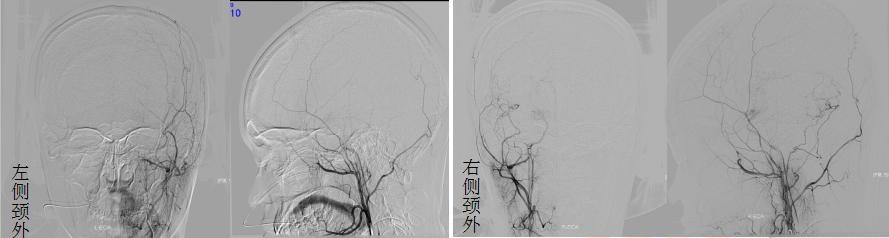

▲左侧脑血管重建术后3个月复查

仔细考虑之后,佳佳决定先接受左侧脑血管重建术(脑-硬脑膜-动脉-颞肌血管融合术)。术后回家休养了3个月后,佳佳遵医嘱到院复查。复查ASL序列提示右侧大脑半球、左侧额顶叶仍示多发片状低灌注区,左侧额颞岛叶灌注较前增高、明显代偿;DSA提示右侧颈外动脉向颅内无代偿,左侧颈外动脉向颅内代偿明显,颅内供血增加。